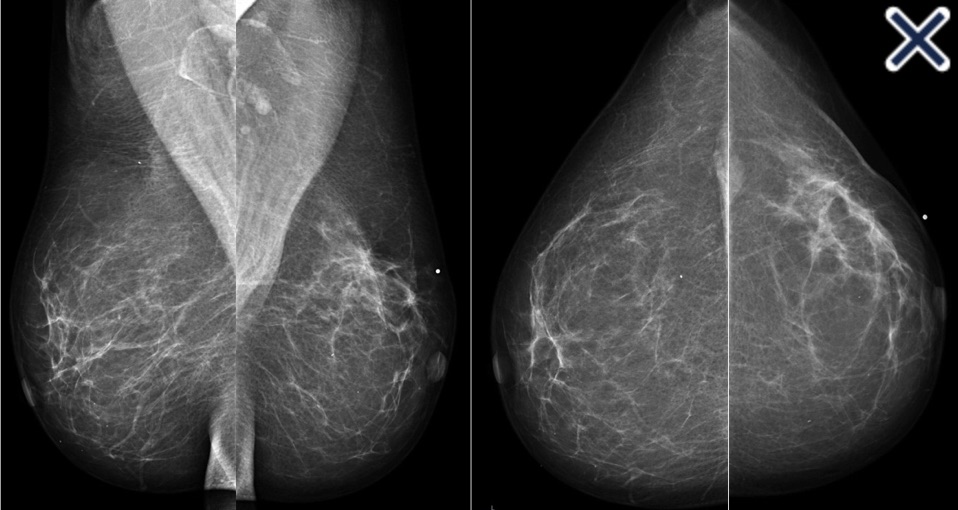

- Diffusely invasive carcinoma:

- Has a mammographic appearance of:

- Diffuse architectural distortion

- Usually involving a large area:

- With no central tumor mass and no calcifications

- It sometimes has the appearance of:

- A “spider’s web” (Image 1)

- The diffusely infiltrating cancer forms concave contours with the surrounding fat in a manner similar to normal fibroglandular tissue (Images 2 a-b)